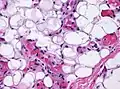

Small vessels in adipose tissue The vessels typically contain hyaline or fibrin (pictured) thrombi[3]

The vessels typically contain hyaline or fibrin (pictured) thrombi[3]